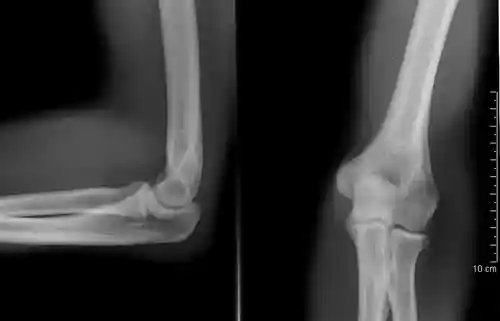

The elbow undergoes dynamic development of ossification centers through infancy and adolescence, with the order of both the appearance and fusion of the apophyseal growth centers being crucial in assessment of the pediatric elbow on radiograph, in order to distinguish a traumatic fracture or apophyseal separation from normal development. The order of appearance can be understood by the mnemonic CRITOE, referring to the capitellum, radial head, internal epicondyle, trochlea, olecranon, and external epicondyle at ages 1, 3, 5, 7, 9 and 11 years. These apophyseal centers then fuse during adolescence, with the internal epicondyle and olecranon fusing last. The ages of fusion are more variable than ossification, but normally occur at 13, 15, 17, 13, 16 and 13 years, respectively.[16] In addition, the presence of a joint effusion can be inferenced by the presence of the fat pad sign, a structure that is normally physiologically present, but pathologic when elevated by fluid, and always pathologic when posterior.[17]

There are three bones at the elbow joint, and any combination of these bones may be involved in a fracture of the elbow. Patients who are able to fully extend their arm at the elbow are unlikely to have a fracture (98% certainty) and an X-ray is not required as long as an olecranon fracture is ruled out.[27] Acute fractures may not be easily visible on X-ray.[28]